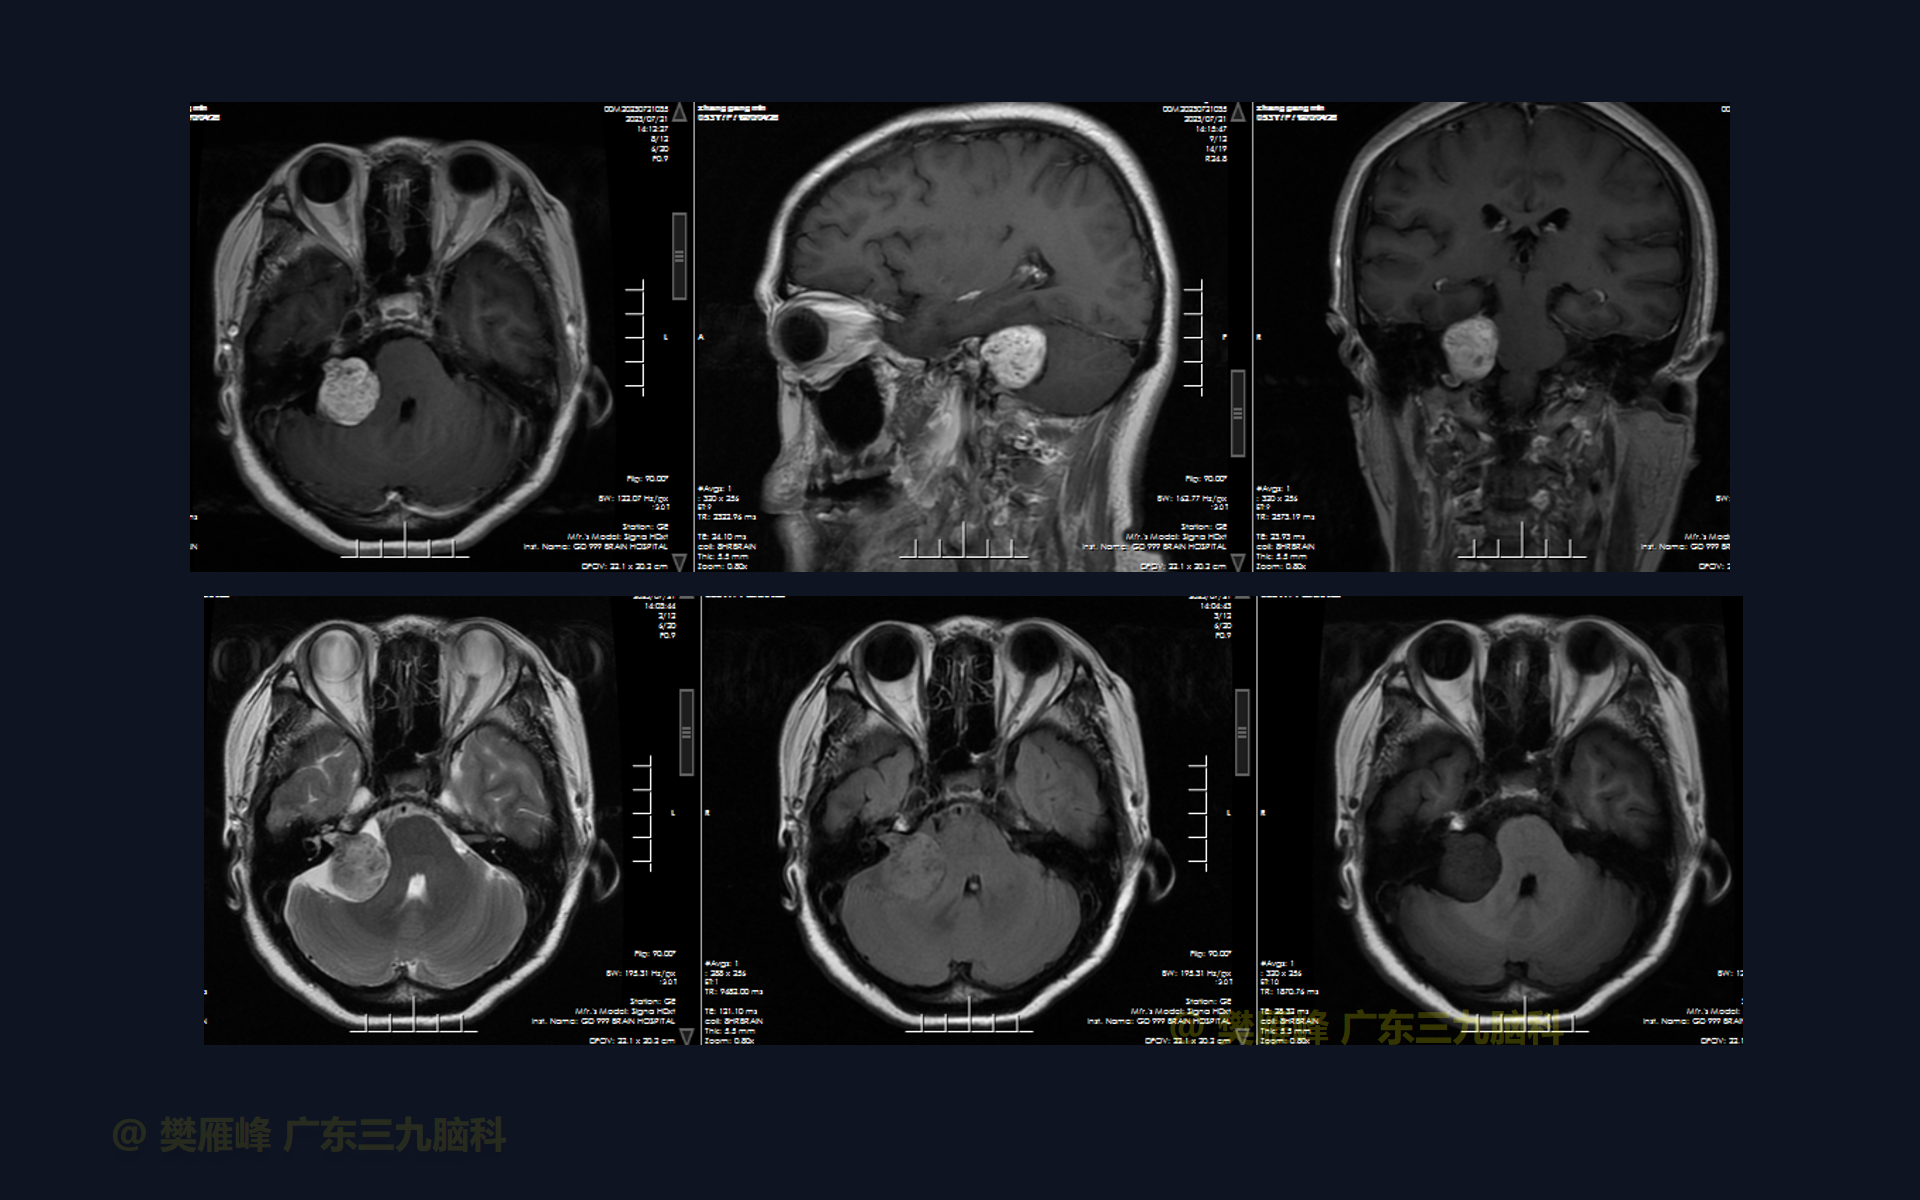

在这个二维手术视频中,展示了一种经枕下乙状窦后入路肿瘤包膜下分离并保留面神经。患者是一名53岁的男性,有1月的左耳听力下降、无步态不平衡病史,神经影像学显示右侧桥小脑角区T1低信号,T2不均匀高信号,DWI序列呈等、低信号,增强不均匀强化的听神经瘤。他接受了经乙状窦后入路保留面神经的方法,以实现肿瘤全切除。术后轻微面瘫,听力同术前改变,神经影像学显示肿瘤全部切除。我们展示了包膜下切除肿瘤和保护面神经的细微差别和技术要点。

在这段手术视频中,展示了一名53岁男性的病例,他因右耳听力下降1月余发现的右侧听神经瘤